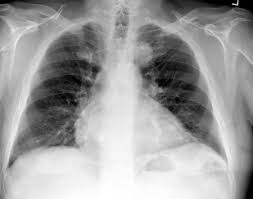

A description of popcorn calcification—meaning images that look like popcorn on a ct. Eccrine angiokeratomatous hamartoma combined with solitary angiokeratoma or verrucous venous malformation: Residents and fellows contest rules | international ophthalmologists contest rules. Endobronchial hamartoma resected by rigid bronchoscope. Report of two cases and comprehensive review of the literature.

A large hamartoma of the spleen. A rare cause of bronchial occlusion. Hamartoma, benign tumourlike growth made up of normal mature cells in abnormal number or distribution. A hamartoma (from greek hamartion bodily defect) is a benign (noncancerous) tumorlike malformation made up of an abnormal mixture of cells and tissues found in areas of the body where growth occurs. A hamartoma is a focal malformation that resembles a neoplasm in the tissue of its origin. This is not a malignant tumor, and it grows hamartomas, while generally benign, can cause problems due to their location. This zone shows sheets of immature cells with bland, ovoid vesicular nuclei. It is considered a developmental error and can occur at a number of sites. A mass resembling a tumor that represents anomalous development of tissue natural to a part or organ rather than a true tumor. Breast hamartomas are responsible for roughly 5 percent of benign breast masses. A large hamartoma of the spleen. Hamartomas can be difficult to distinguish from cancers but do have some characteristics that set them apart. Residents and fellows contest rules | international ophthalmologists contest rules.

Hamartoma is a benign (not cancer) growth made up of an abnormal mixture of cells and tissues normally found in the area of the body where the a lesion first described by german pathologist eugen albrecht in 1904, hamartomas are generally benign tumors that may occur in the lungs, skin. A description of popcorn calcification—meaning images that look like popcorn on a ct. The hamartoma can occur in almost any organ and is usually asymptomatic. High magnification shows the 3 components of fhi. In radiology, hamartomas often mimic malignancy. Jump to navigation jump to search. Is that hamartoma is (pathology) a benign mass of disorganized tissue while teratoma is (pathology) a benign or malignant tumour, especially of the gonads, that arises from germ cells and consists of different types of tissue such as skin, hair, or muscle. When located on the skin, especially the face or neck, they can be extremely disfiguring, as.